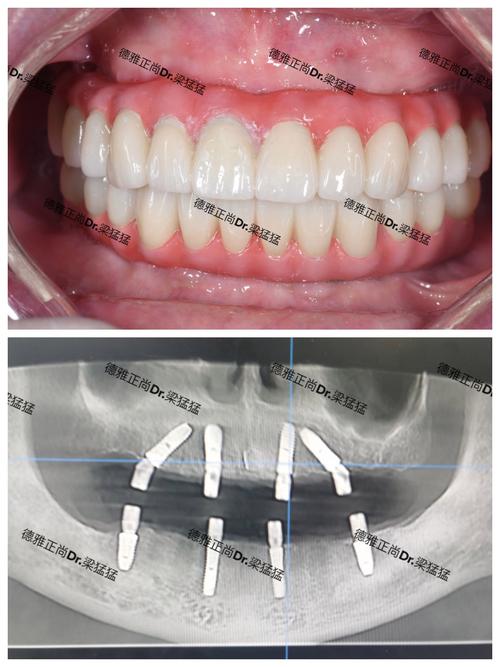

可通过大众点评、知乎、小红书等平台查看患者评价,重点关注“术后效果”“医生沟通”“服务细节”等内容;要求机构提供相似病例的术前术后对比照,直观评估医生技术。